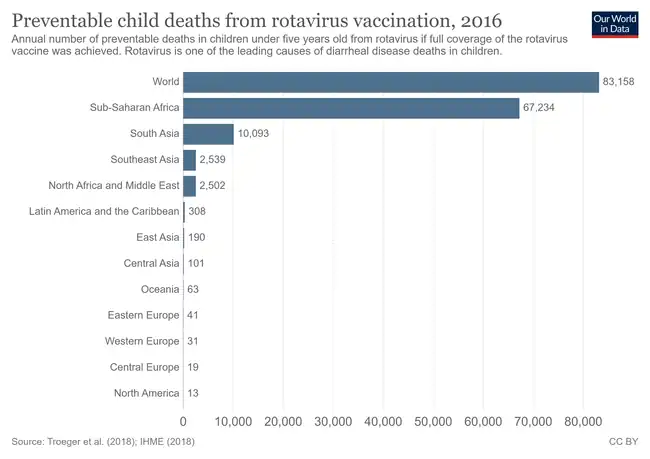

The seasonal variation of rotavirus A infections in England: rates of infection peak during the winter months.[144] Preventable child deaths from rotavirus vaccination, 2016. Annual number of preventable deaths in children under five years old from rotavirus if full coverage of the rotavirus vaccine was achieved.[145]

Preventable child deaths from rotavirus vaccination, 2016. Annual number of preventable deaths in children under five years old from rotavirus if full coverage of the rotavirus vaccine was achieved.[145]